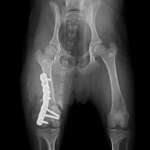

幼犬の大腿骨遠位の骨折です。幼犬は治癒能力が高く、仮骨の形成が早期に起こります。しかしながらこの時期は骨質が大変柔らかく固定には注意が必要です。本来であれば成長板をまたぐ固定は避けたいところですが、やむを得ず軽量のTitanium Locking Plateを用いて固定術を行いました。早期に抜釘することになります。